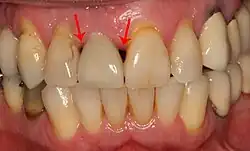

The gingiva surrounding a tooth has a 2–3 mm band of bright pink, very strong attached mucosa, then a darker, larger area of unattached mucosa that folds into the cheeks. When replacing a tooth with an implant, a band of strong, attached gingiva is needed to keep the implant healthy in the long-term. This is especially important with implants because the blood supply is more precarious in the gingiva surrounding an implant, and is theoretically more susceptible to injury because of a longer attachment to the implant than on a tooth (a longer biologic width).[64]: 629–633

When an adequate band of attached tissue is absent, it can be recreated with a soft tissue graft. There are four methods that can be used to transplant soft tissue. A roll of tissue adjacent to an implant (referred to as a palatal roll) can be moved towards the lip (buccal), gingiva from the palate can be transplanted, deeper connective tissue from the palate can be transplanted or, when a larger piece of tissue is needed, a finger of tissue based on a blood vessel in the palate (called a vascularized interpositional periosteal-connective tissue (VIP-CT) flap) can be repositioned to the area.[58]: 113–188 Xenogeneic collagen matrices are used for gingival augmentation after dental implantation.[65][66]

Additionally, for an implant to look esthetic, a band of full, plump gingiva is needed to fill in the space on either side of implant. The most common soft tissue complication is called a black triangle, where the papilla (the small triangular piece of tissue between two teeth) shrinks back and leaves a triangular void between the implant and the adjacent teeth. Dentists can only expect 2–4 mm of papilla height over the underlying bone. A black triangle can be expected if the distance between where the teeth touch and bone is any greater.[50]: 81–84